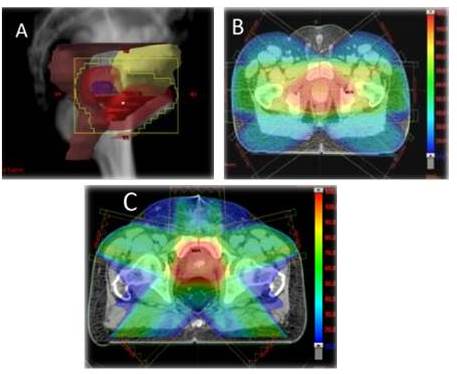

GINECOLÓGICAS

RAVM ofrece al igual que en otras áreas la posibilidad de obtener altas dosis en el volumen blanco y minimizar al mismo tiempo la dosis a estructuras riesgo. Se usan Rayos X de 6 MV y el paciente se posiciona decúbito supino. Se emplean 2 arcos axiales (camilla en 0°) parciales con ángulos de inicio y finalización de 150° y 210° para de esta manera minimizar la dosis en el recto. Al igual que en los casos anteriores existe una reducción de alrededor de 14 min.

En la siguiente Figura se observa el plan de tratamiento en plano axial, coronal y sagital para el tratamiento de una lesión en cuello uterino.